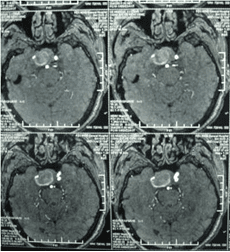

頸內(nèi)動(dòng)脈虹吸段巨大動(dòng)脈瘤(約3cm ×3cm

顱內(nèi)動(dòng)脈瘤是指腦動(dòng)脈的局部性異常擴(kuò)大,多在腦底動(dòng)脈的分叉處或分支的夾角向外突出,多呈囊狀。TCD對顱內(nèi)動(dòng)脈瘤的總檢出率為67 %,動(dòng)脈瘤>1cm的檢出率為82 %。TC D 對較大動(dòng)脈瘤的檢測有其特征性表現(xiàn),其典型表現(xiàn)為:瘤體內(nèi)血流速度明顯低于載瘤動(dòng)脈血流速度,其收縮峰陡峭或多峰不整,舒張期末流速極低或斷流,PI 值增高,多為雙向血流,聲頻低鈍,似撞擊樣轟鳴音。